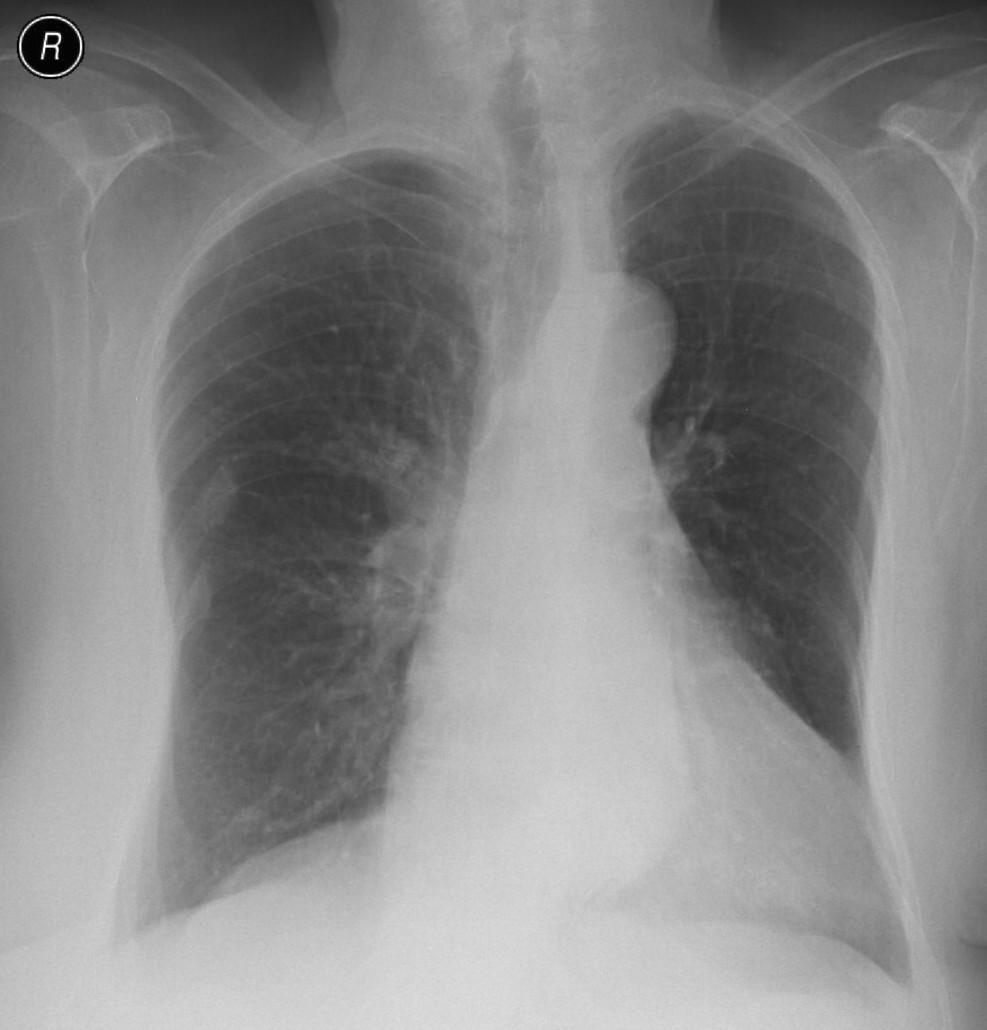

16. Right lobar pneumonia. a.) PA b.) lateral radiograph.